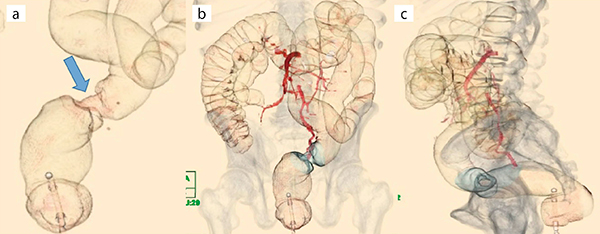

図3は,60歳,男性,大腸がん疑い精査目的にて施行した症例である。肛門より15.8cmの直腸に,長軸径27.2mm,CT値45HU,全周性の壁肥厚がVDCBEで明瞭に観察できる(図3 a)。また,マルチレイヤー機能,マルチボリューム機能により腫瘍や血管,骨の情報を付加することで,解剖学的な病変部の位置が正確に判断できる(図3 b,c)。病変部の側面変形像は注腸X線検査における深達度診断が適合でき(図3 a),仙骨の情報を付加した側面像は直腸病変の部位診断に有用である(図3 c)。直腸(Rs)のapple core signを,VDCBEの作成により位置関係を含め明瞭に描出できた一例である。

図3 仮想注腸画像:VDCBE

a:air image(apple core sign↓)

b:air image 正面像〔マルチレイヤー(上腸間膜動脈,下腸間膜動脈)+マルチボリューム(骨情報)〕

c:air image 側面像(仙骨情報)